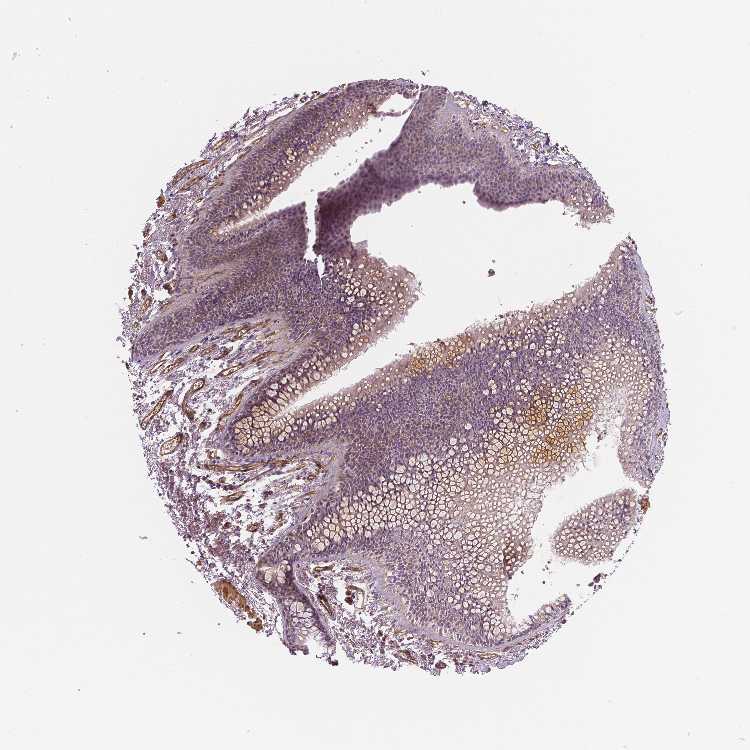

SOFT TISSUE 1 - Antibody stainingi

Antibody staining in the annotated cell types in the current human tissue is reported as not detected, low, medium, or high, based on conventional immunohistochemistry profiling in selected tissues. This score is based on the combination of the staining intensity and fraction of stained cells.

Each image is clickable and will lead to virtual microscopy that enables deeper exploration of all samples and also displays staining intensity scores, fraction scores and subcellular localization as well as patient and tissue information for each sample.

Antibody HPA011740Antibody HPA014290Antibody CAB068189Antibody CAB068190

Chondrocytes LowNot detectedNot detected-

SOFT TISSUE 2 - Antibody stainingi

Fibroblasts MediumNot detectedNot detectedNot detected

Peripheral nerve Not detectedNot detectedNot detectedNot detected